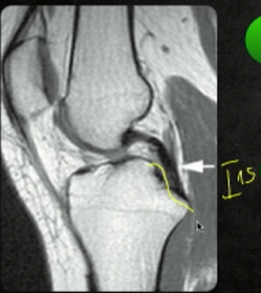

Exames de imagem?

A

RX perfil com estresse posterior

- Translação > 8mm = LLCP

TC: avaliar avulsões ósseas

RNM:

- Hipossinal em todas sequências (homogêneo)

Origem tibial do LCP?

“Taça de champagne”

10mm distal a superfície articular